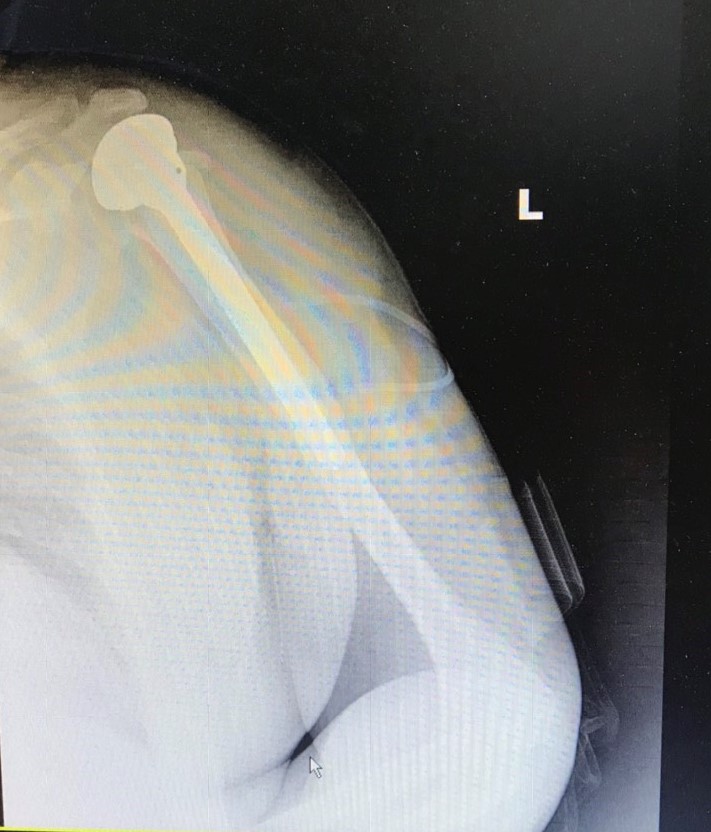

Phối hợp cùng bác sĩ chuyên gia, bác sĩ Khoa Ngoại, Bệnh viện đa khoa Quốc tế Hải Phòng đã thực hiện ca mổ một cách nhanh chóng và thuận lợi. Phần chỏm xương cánh tay vỡ nát vụn đã được các phẫu thuật viên lấy bỏ và thay thế bằng chỏm xương nhân tạo, tái tạo lại giải phẫu khớp vai. Ngay sau mổ, bệnh nhân đã được các y bác sĩ bệnh viện chăm sóc và hướng dẫn tập phục hồi chức năng.

- Hình ảnh thay chỏm xương cánh tay bên trái sau mổ cho bệnh nhân